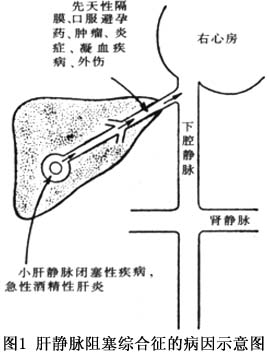

(2)鄰近臟器病變(包括炎症、創傷、肝佔位性病變等),造成血管受壓或血流受阻(圖1)。